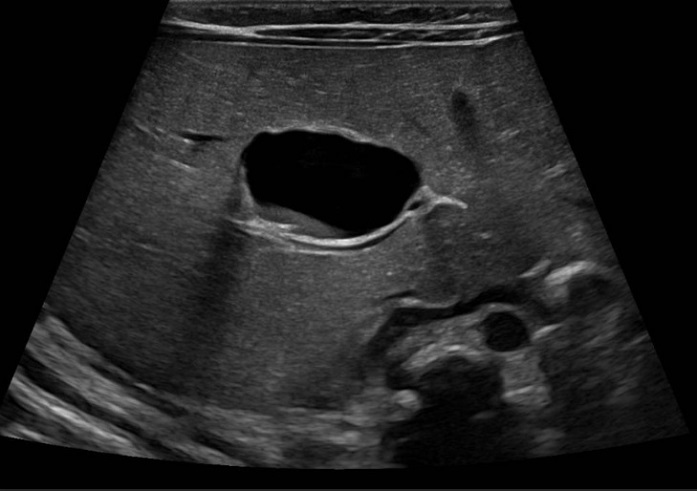

Lactante de 1 mes y 27 días derivada a la consulta de Digestivo Infantil para seguimiento de quiste hepático congénito simple. En la ecografía del segundo trimestre, realizada en su hospital de origen, se objetiva una imagen quística a nivel abdominal. Por este motivo es derivada a nuestro centro, donde, en la semana 25, se realiza nueva ecografía que muestra datos sugestivos de quiste de colédoco: imagen quística de 9 x 9 mm de diámetro que se localiza en hemiabdomen derecho fetal, inmediatamente por encima de la vesícula biliar, contactando con ella en su porción más superior (Figura 1).

| Figura 1. Quiste hepático congénito. Ecografía prenatal en la que se visualiza una imagen quística abdominal |